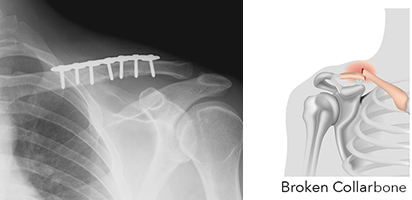

A doctor can diagnose it by a clinical examination and it can usually be confirmed on X-ray. With an Open fracture the bone will protrude from the shoulder. Closed fracture is usually diagnosed with x-rays.

Treatment may vary, depending on the type of fracture. If you have a clavicle fracture that is not displaced meaning that the bones align even with the fracture – you may be treated conservatively in a sling. The sling will be worn for 6 weeks where after an x-ray will be taken to see if acceptable bone formation and healing has taken place. If you have a displaced fracture, in other words if the bones are not aligning properly, you will require surgery to align and keep the bones aligned for healing.

Under general anaesthesia, and Open Reduction Internal Fixation (ORIF) is done. An incision is made and a plate and screws are fixated to align the Clavicle and keep them in place.